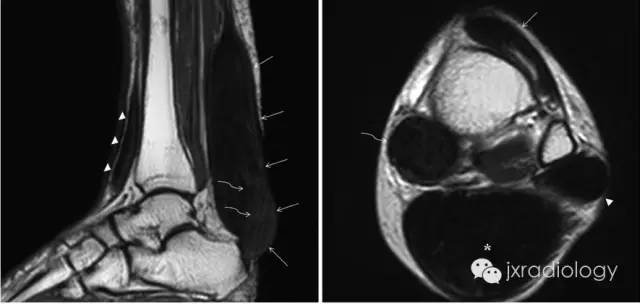

影像学表现:MRI典型病变的信号为跟腱明显梭形增粗 T1WI 像上呈顺跟腱长轴的类似肌肉的信号,表现为毛刷样改变,在 T2WI 像上也呈较低信号影,其内有斑点状短 T1 长 T2 较高信号影,T2WI 压脂像高信号区为低信号。CT:双侧跟腱部对称或单侧类梭形软组织肿块,向外膨隆,类似于肌肉密度,CT 值约 60~80Hu,与正常肌腱无法区分。